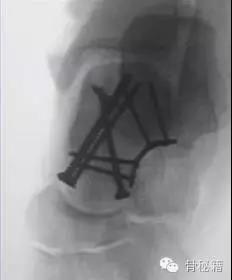

除去关节面的地方,就是我们最适合置放内固定的地方主要位于内侧和外侧

手术指证移位的体部骨折和II-IV型(2mm以上)的颈部骨折移位

对于颈部的骨折,如果一侧钢板的位置不佳,则容易造成另外一侧的骨折裂开所以最好的固定是一侧用钢板固定,另外一侧可采用螺钉进行加压,避免另外一侧开口

要点!!1、骨折严重合并脱位的一定要早期临时外架牵引复位和维持一定要早期临时外架牵引复位和维持一定要早期临时外架牵引复位和维持重要的说三遍2、尽量保护血运,用单侧入路3、尽量避免关节面内置物4、注意皮肤软组织情况